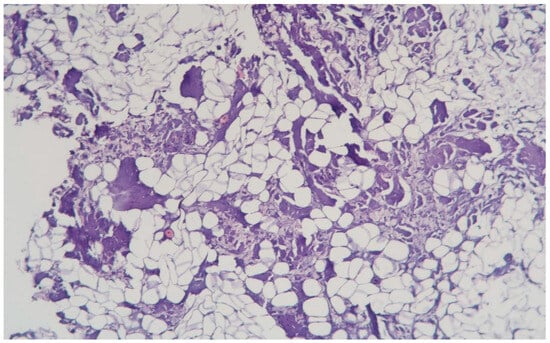

3.1.8. Clinical Case 8: Adipose Tissue Dissection Area, 15 W (See Figure 9)

Description: The coagulative necrosis of the adipose tissue was primarily along the septa. The vessels in the subcutaneous adipose tissue were congested; small-caliber vessels were coagulated, while larger vessels showed necrosis of the perivascular space, polarization, and sloughing of endothelial cells. Inflammatory changes were absent.

Figure 9.

Changes in subcutaneous adipose tissue following exposure to the thulium laser at 15 W 75 Hz. H&E staining, 10× objective magnification.